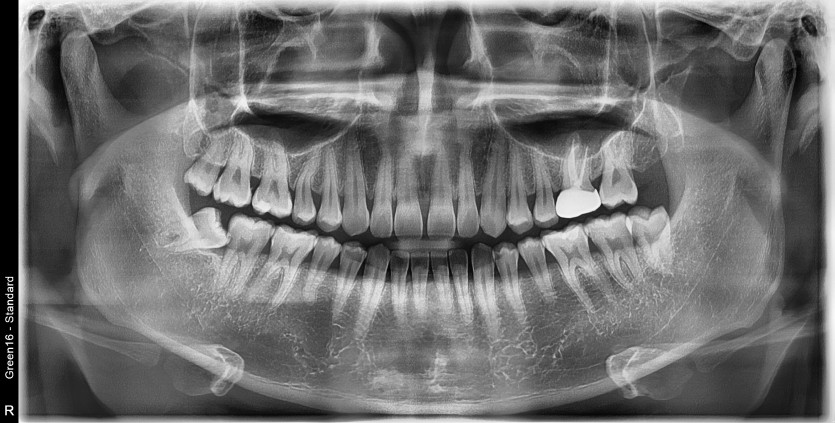

#18,48 사랑니 발치

구강 외과 전문의가 당일 발치했습니다.